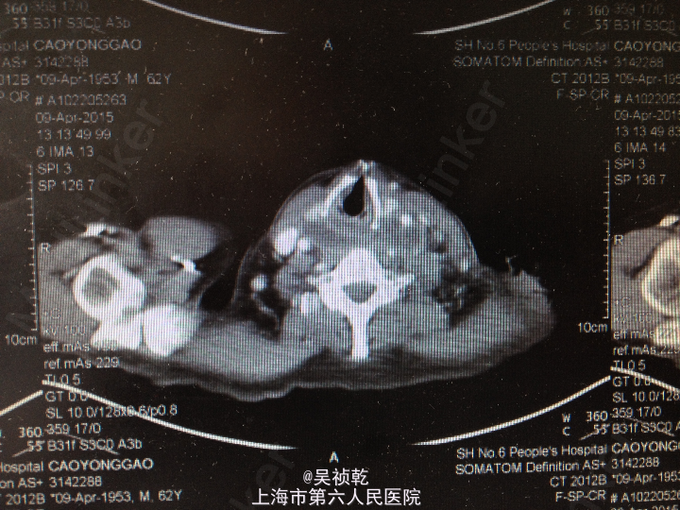

查体:神志清醒,呼吸稍促,推入病房,发育正常,营养良好,自主体位。皮肤粘膜:无黄染,无瘀点瘀斑,无贫血貌,无肝掌,无蜘蛛痣。淋巴结:全身浅表淋巴结可触及肿大。双侧颌下淋巴结肿大,左侧颈部肿大,皮肤红肿,皮温偏高,局部有波动感。头颈部:无头颅畸形,无巩膜黄染,无结膜苍白 ,口唇无紫绀,无扁桃体肿大。颈软,气管居中,甲状腺无肿大,无颈静脉怒张。胸部:胸廓无畸形,心率105次/分, 节律齐,无杂音,两肺呼吸音清,未及啰音。腹部:腹部平坦,腹壁柔软,全腹无压痛、无反跳痛,肝脏肋下未触及,脾肋下未触及,肝区无叩击痛,肾区无叩击痛。无移动性浊音,肠鸣音正常。肛门、直肠及外生殖器: 正常。脊柱与四肢:脊柱无畸形,四肢无畸形,四肢活动自如。神经系统:生理反射存在,病理反射未引出。 辅检:2015-4-8 血气检验报告:二氧化碳分压 34.7 mmHg ↓,氧分压 60.9 mmHg ↓,氧饱和度 91.8 % ↓。门诊化验检验报告:凝血酶原时间 13.1 秒 ,国际标准化比率 1.19 ↑,部分凝血活酶时间 30.4 秒 ,D二聚体 1.13 mg/L FEU ↑,纤维蛋白(原)降解产物 6.4 mg/L ↑。 生化检验报告:肌钙蛋白-I 0.013 ,CKMB 1.4 ug/L ,肌红蛋白 28.6 ug/L 。 生化检验报告:血清钾(干式) 4.5 mmol/L ,血清钠(干式) 137 mmol/L ↓,血清氯(干式) 94 mmol/L ↓,总蛋白(干式) 66 g/L ,白蛋白(干式) 32 g/L ↓,谷丙转氨酶(干式) 26 U/L ,谷草转氨酶(干式) 16 U/L ,γ-谷氨酰酶(干式) 19 U/L ,碱性磷酸酶(干式) 103 U/L ,总胆红素(干式) 16 μmol/L ,尿素(干式) 7.5 mmol/L ↑,肌酐(干式) 67 μmol/L ,尿酸(干式) 154 μmol/L ↓,淀粉酶(干式) <30 U/L ↓,血糖(干式) 22.0 mmol/L ↑,B型钠尿肽前体(proBNP) 199.80 ng/L ↑。 2015-4-9 血常规检验报告:白细胞 13.2 X10^9/L ↑,红细胞 3.76 X10^12/L ↓,血红蛋白 125 g/L ↓,细胞比积 35.8 % ↓,血小板 261 X10^9/L ,淋巴细胞百分比 4.7 % ↓,中性细胞百分比 84.4 % ↑。糖尿病医学中心检验报告:糖化血红蛋白 12.40 % ↑。 颈部超声示:双侧颌下淋巴结肿大,左侧颈后软组织结构紊乱,内混合回声及肿大淋巴结,考虑炎性改变可能,建议治疗后复查。 颈部CT:1.咽后间隙、左侧咽旁间隙及颈动脉鞘软组织明显肿胀、渗出,颈部多发肿大淋巴结,考虑炎症可能大,请结合临床并门诊增强CT评估。2.左侧甲状腺小结节可能,请结合临床,必要时随访。 2015-4-9 颈部增强CT示:颈部及胸腔纵隔脓肿形成。 2015-4-8引流分泌物培养结果: 肺炎克雷伯菌。

患者入院时诊断为:1.左颈部脓肿,颈部软组织感染,纵膈脓肿形成。2.糖尿病。 入院后予对症处理:1.加强抗感染,予万古霉素+磷霉素联合。2.床边行脓肿切开引流,引流液送培养。2、予吸氧、禁食、营养支持等对症治疗。3.病情危重,告知家属相关风险,予告病危。4.进一步完善颈部及胸部增强CT,病请五官科会诊。 2015.04.09CT提示颈部,咽后壁及胸腔纵隔脓肿形成,故请五官科及胸外科会诊,会诊意见为:手术切开引流。故于4.9全麻下行颈部脓肿清创引流术。 手术过程:患者取仰卧位,肩部垫高,全麻达成后,常规消毒铺巾。在胸骨切迹上约两横指处顺皮纹方向作弧形领式切口,长约8cm。依次切开皮肤、皮下组织和颈阔肌。游离颈阔肌深面间隙,在其深面用电刀分离皮瓣,上至甲状软骨切迹,下至胸骨切迹,两侧越过胸锁乳突肌前缘。分离右侧胸锁乳突肌,分离至咽后间隙,咽后间隙内见大量脓液,予双氧水,稀碘伏水,及生理盐水彻底冲洗脓腔。术中请胸外科会诊认为目前上纵隔脓肿暂无需处理。左右各置一根颈部引流管;仔细止血;清点器械无误后,缝合皮下及皮肤层。术中出血少未输血,术程顺利,病人安返。 术后诊断:1.左颈部脓肿,颈部软组织感染,纵膈脓肿形成。2.糖尿病。3.全身感染症状。4.吞咽困难。 术后结合药敏结果,继续予万古霉素+磷霉素联合抗炎,引流管予生理盐水持续冲洗引流,目前引流液不多,术后一周复查CT见脓肿明显缩小,纵膈脓肿有所缩小,目前治疗方案:1.停用原抗菌方案,换用莫比沙星 0.4 qd 静滴,每次滴注90min;2.每3天复查血象,及时复查颈部CT,治疗5天后再评估,一般情况好可停药随访;3.糖尿病患者,注意血糖变化,监测心功能及肝肾功能。